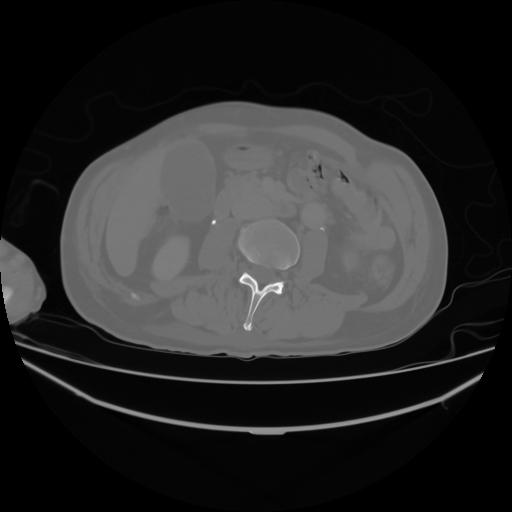

4 CUERPO,CE,Axial,3.0,CUERPO,,